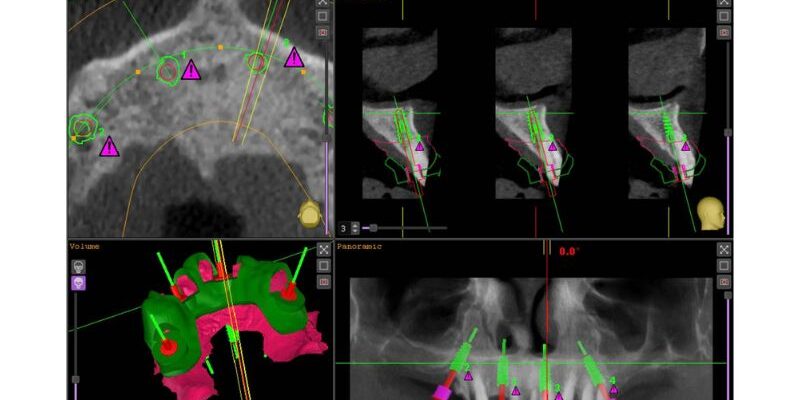

- Recepción de archivos STL + DICOM

- Fusión de escaneado intraoral con TAC

- Planificación conjunta del caso con el clínico (posición, angulación, profundidad)

- Diseño de la guía quirúrgica adaptada al sistema implantológico del profesional